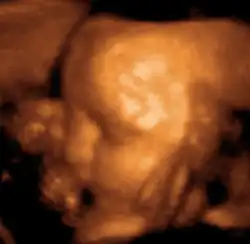

Head of a fetus, aged 29 weeks, in a "3D ultrasound"

The potential for ultrasonic imaging of objects, in which a 3 GHz sound wave could produce resolution comparable to an optical image, was recognized by Sergei Sokolov in 1939. Such frequencies were not possible at the time, and what technology did exist produced relatively low-contrast images with poor sensitivity.[36] Ultrasonic imaging uses frequencies of 2 megahertz and higher; the shorter wavelength allows resolution of small internal details in structures and tissues. The power density is generally less than 1 watt per square centimetre to avoid heating and cavitation effects in the object under examination.[37] Ultrasonic imaging applications include industrial nondestructive testing, quality control and medical uses.[36]

Medical ultrasound is an ultrasound-based diagnostic medical imaging technique used to visualize muscles, tendons, and many internal organs to capture their size, structure and any pathological lesions with real time tomographic images. Ultrasound has been used by radiologists and sonographers to image the human body for at least 50 years and has become a widely used diagnostic tool.[38] The technology is relatively inexpensive and portable, especially when compared with other techniques, such as magnetic resonance imaging (MRI) and computed tomography (CT). Ultrasound is also used to visualize fetuses during routine and emergency prenatal care. Such diagnostic applications used during pregnancy are referred to as obstetric sonography. As currently applied in the medical field, properly performed ultrasound poses no known risks to the patient.[39] Sonography does not use ionizing radiation, and the power levels used for imaging are too low to cause adverse heating or pressure effects in tissue.[40][41] Although the long-term effects due to ultrasound exposure at diagnostic intensity are still unknown,[42] currently most doctors feel that the benefits to patients outweigh the risks.[43] The ALARA (As Low As Reasonably Achievable) principle has been advocated for an ultrasound examination – that is, keeping the scanning time and power settings as low as possible but consistent with diagnostic imaging – and that by that principle nonmedical uses, which by definition are not necessary, are actively discouraged.[44]